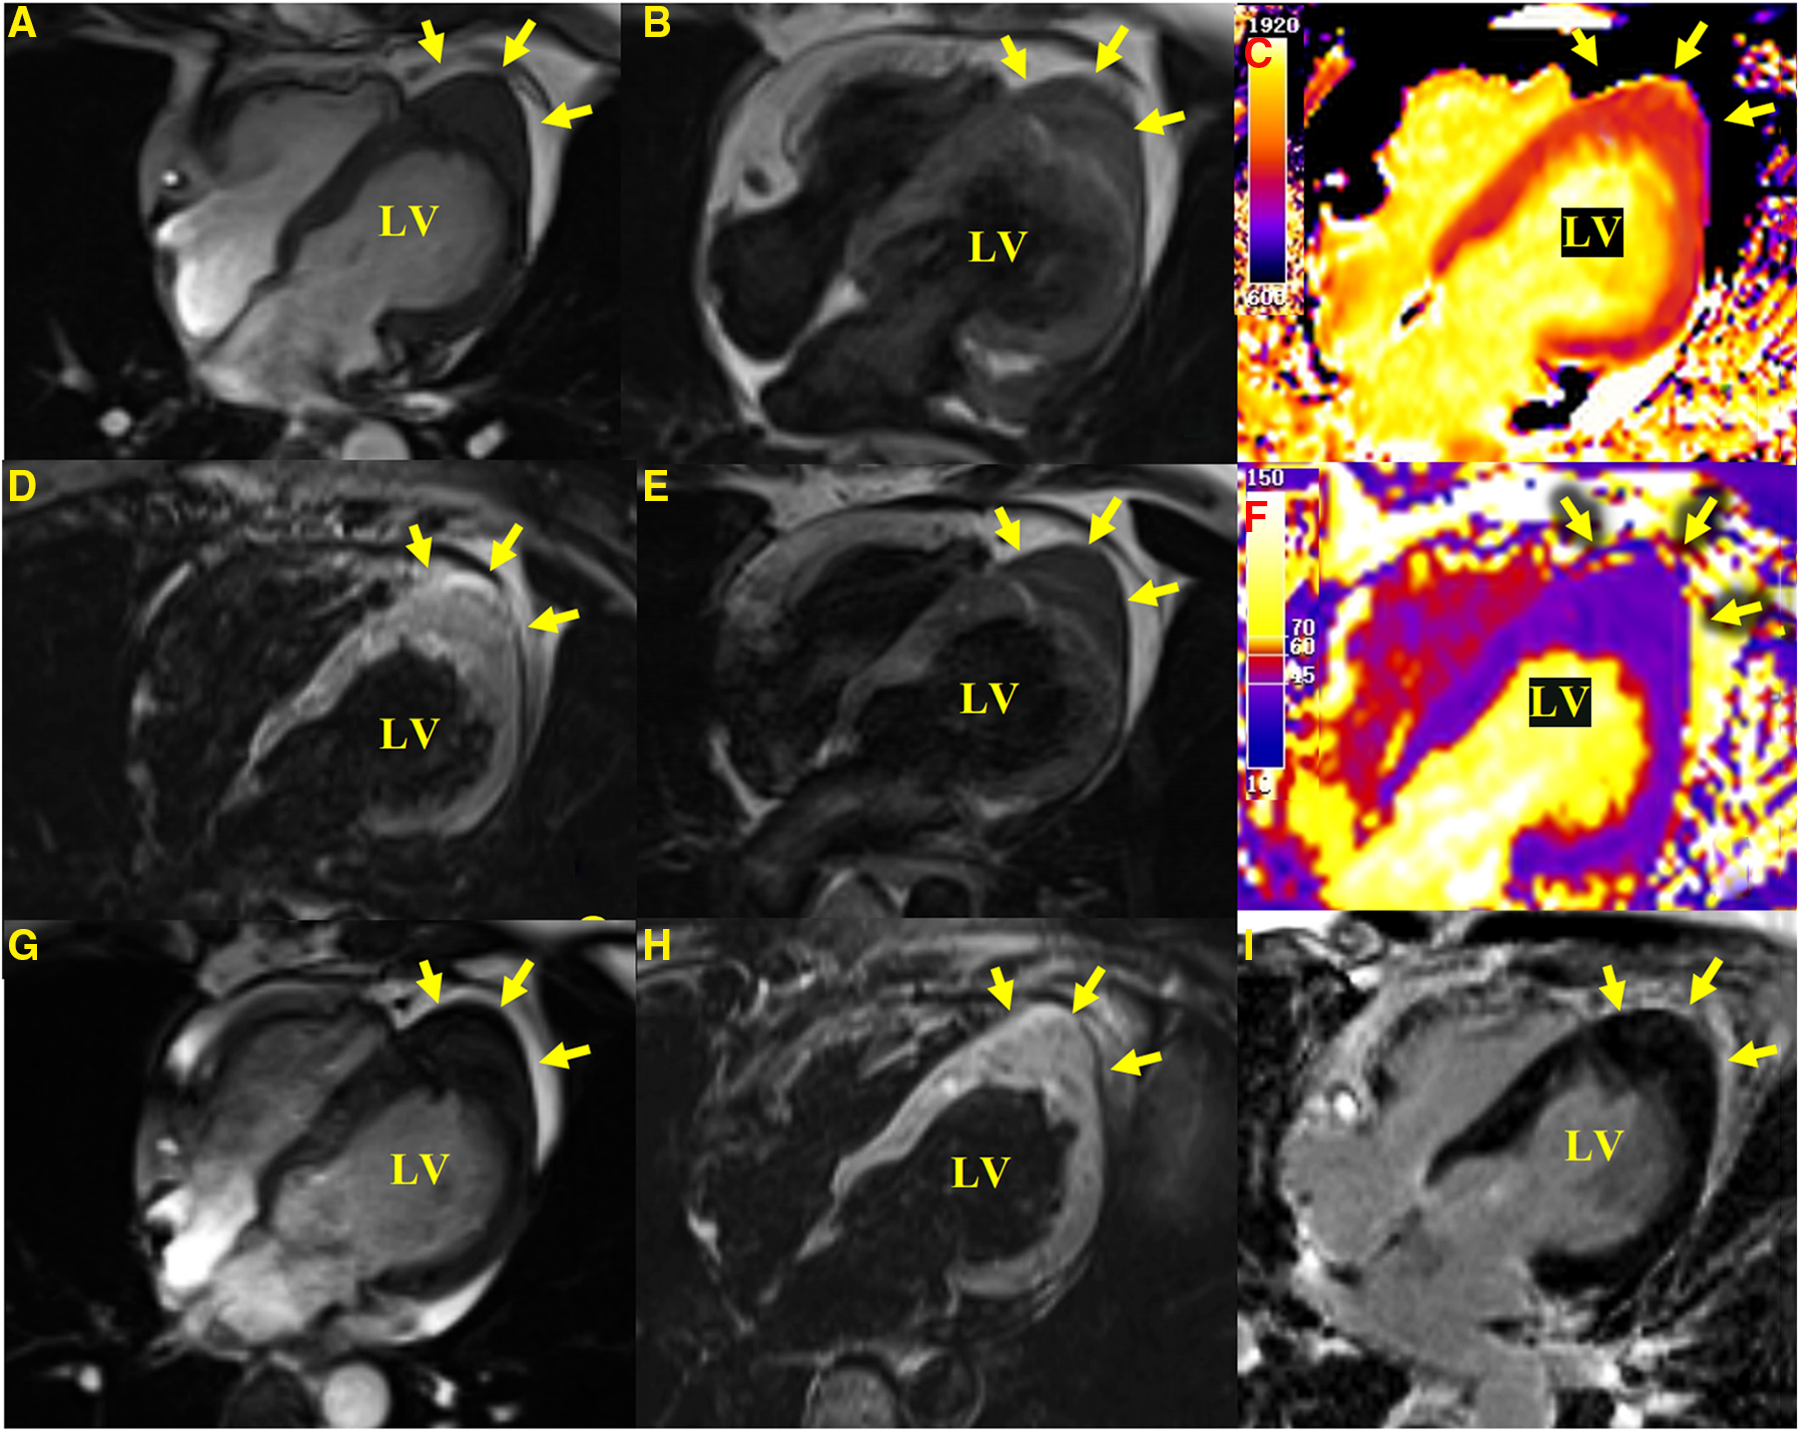

Figure 2

CMR images. Apical hypertrophy with a maximal thickness of 17 mm can be seen in four-chamber views in steady-state free precession cine images (A), a T1-weighted CMR sequence (B), a T2-weighted sequence (E), T1-mapping (C) (the values were approximately 1,210 ms for a normal myocardium and approximately 1,213 ms for the apical portion), a T2-mapping sequence (F) (the values were approximately 41 ms for a normal myocardium and approximately 40 ms for the apical portion), a fat-suppressed T2 sequence (D), and an LGE image (I) reveal similar myocardial tissue characteristics as the normal myocardium. (G,H) show a cine image and a fat-suppressed T2 sequence after 3 months with no significant change in the lesion compared with the initial presentation.

A 41-year-old woman, with a body height of 150 cm and weight of 51 kg, presented with a LV apical hypoechogenic tissue detected by TTE, initially suspected as an LV myocardial tumor (Figure 1). Subsequent CMR examination identified it as focal left ventricular hypertrophy with a mass-like protrusion of the apical myocardium measuring 17 mm in diameter, as shown in four-chamber views at the end diastole (Figure 2). Cine CMR showed that the lesion was contracting with systole and relaxing with diastole coincident with the normal myocardium, with no reverse motion observed (Supplementary Video). The valves demonstrated normal function and flow. The resting LV systolic function was normal, with an LV ejection fraction of 65%. The T1-weighted, T2-weighted, and T1/T2-mapping CMR images demonstrated myocardial characteristics similar to surrounding normal tissue (Figure 2). A linear area of hyperintensity at T1-weighted and T2-weighted CMR was seen within the lesion, becoming hypointense in fat-suppressed T2 images, suggesting myocardial fat deposition. The first-pass perfusion did not show filling defects, and late gadolinium enhancement (LGE) was unremarkable (Figure 2).